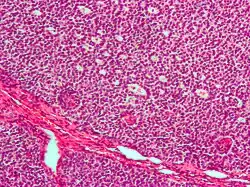

| Micrograph of a granulosa cell tumour, a type of sex-cord–gonadal stromal tumour. H&E stain. | |